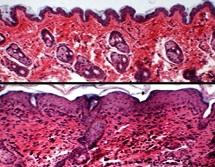

ECZÉMA : Granzyme B, l’enzyme qui ronge la barrière cutanée

Actualité publiée le 03/12/2018ECZÉMA : La filaggrine cette protéine clé de la barrière cutanée

Actualité publiée le 17/03/2018